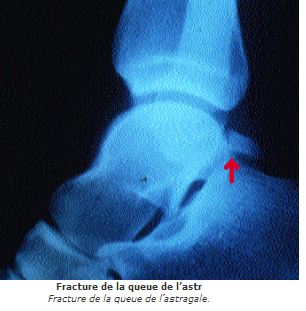

- les lésions de la queue de l'astragale ou syndrome du carrefour postérieur

Entésophytose localisée, remaniements du tubercule postéro externe de l'Astragale qui prend un aspect flou, irrégulier, fragmenté et qui peut aller jusqu'à se séparer du corps de l'Astragale; à différencier de l'os trigone physiologique par non fusion du tubercule postéro externe qui existe chez 80% des footballeurs et qui ne s'est pas soudé du fait des microtraumatismes répétés depuis l'enfance.